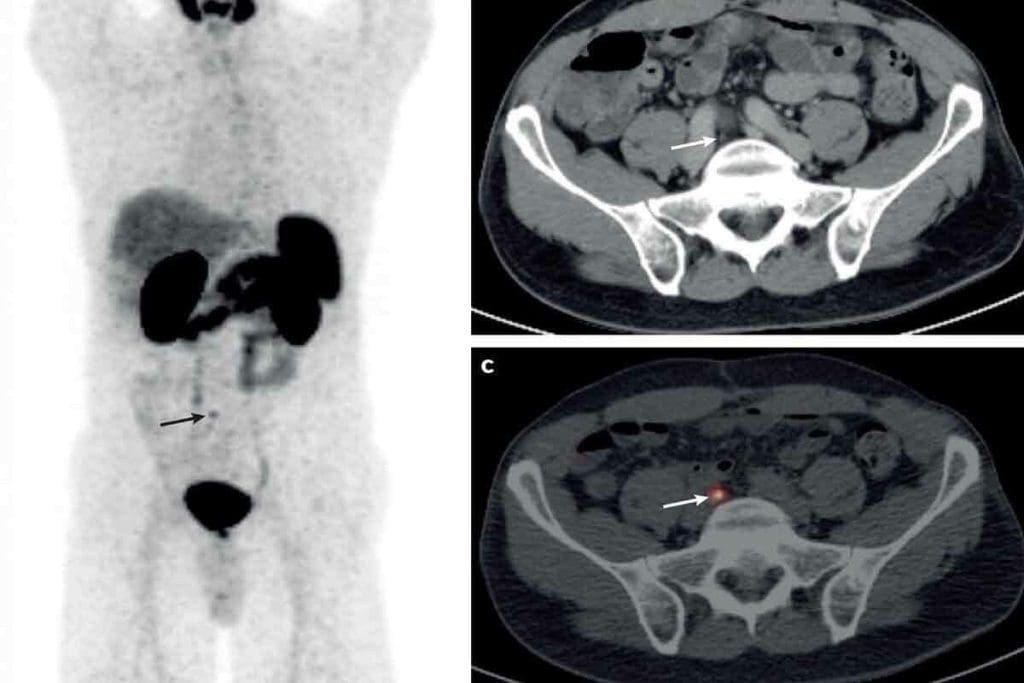

PET/CT scans combine both. They offer detailed anatomy and metabolic info in one scan. This makes diagnosis more accurate and is now common in cancer care.

The Difference Between PET CT Scan and CT Scan for Staging

PET/CT scans combine PET and CT scans. They give both functional and anatomical details. This combo is better at finding cancer spread and local disease than CT scans alone.

In summary, CT scans are great for body details, while PET scans show tumor activity. Together in PET/CT scans, they improve cancer staging. This makes PET/CT scans a top choice for many cancers.

Key Difference #7: The Power of Combined PET/CT Imaging

The fusion of PET and CT scans into one system has changed how we diagnose cancer. This new method combines CT’s detailed images with PET’s metabolic insights. It gives a deeper look into the disease.

How Integration Enhances Diagnostic Accuracy

Combined PET/CT imaging significantly enhances diagnostic accuracy. It offers both the structure from CT scans and the function from PET scans. This mix helps in:

• Precise localization of tumors

• Accurate assessment of tumor metabolism

• Improved detection of cancer spread